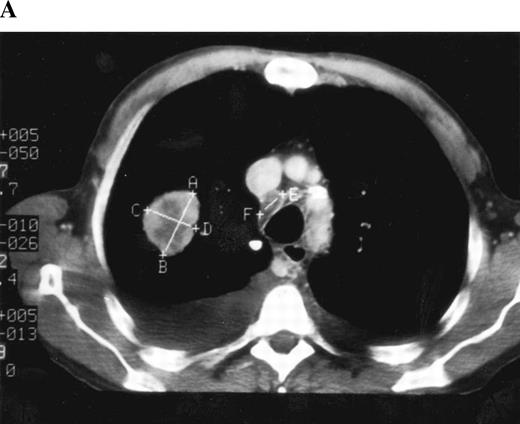

• CT scans of the thorax, abdomen, and pelvis should be contiguous throughout the anatomic region of interest. As a rule of thumb, the minimum size of the lesion should be no less than double the slice thickness. Lesions smaller than this are subject to substantial “partial volume” effects (i.e., size is underestimated because of the distance of the cut from the longest diameter; such a lesion may appear to have responded or progressed on subsequent examinations, when, in fact, they remain the same size [Fig. 1]). This minimum lesion size for a given slice thickness at baseline ensures that any lesion appearing smaller on subsequent examinations will truly be decreasing in size. The longest diameter of each target lesion should be selected in the axial plane only.

The type of CT scanner is important regarding the slice thickness and minimum-sized lesion. For spiral (helical) CT scanners, the minimum size of any given lesion at baseline may be 10 mm, provided the images are reconstructed contiguously at 5-mm intervals. For conventional CT scanners, the minimum-sized lesion should be 20 mm by use of a contiguous slice thickness of 10 mm.

A) Computed tomography (CT)“ scannogram” of the thorax with a simulated 20-mm lesion in the right mid-zone. B) CT “scannogram” of the thorax with contiguous slices of 10-mm thickness. Each volume within the slice thickness is scanned, and the average attenuation coefficient (i.e., density of multiple small cubes [voxels]) is represented spatially in two dimensions (pixels) as a cross-sectional image on a gray scale. It is important to note each line on the figure is a spatial representation of the average density for the structures that pass through that slice thickness, and the line does not represent a thin“ cut” through it at that level. Therefore, a lesion of at least 20 mm will appear about its true diameter on at least one image because sufficient volume of the lesion is present so as not to average it down substantially. C) CT scannogram performed at 15-mm intervals. Depending on how much of the tumor is within the slice thickness, the average density may be substantially underestimated, as in the upper of the two lesions, or it may approximate the true tumor diameter, lower lesion. This is an oversimplification of the process but illustrates the point without going into the physics of CT reconstruction. D) CT scannogram performed at 24-mm intervals and of 10-mm thickness. The lesion may be imaged through its diameter, it may be partially imaged, or it may not be imaged at all. This is the equivalent of imaging a very small lesion and trying to determine whether its true diameter has changed from one examination to the next.